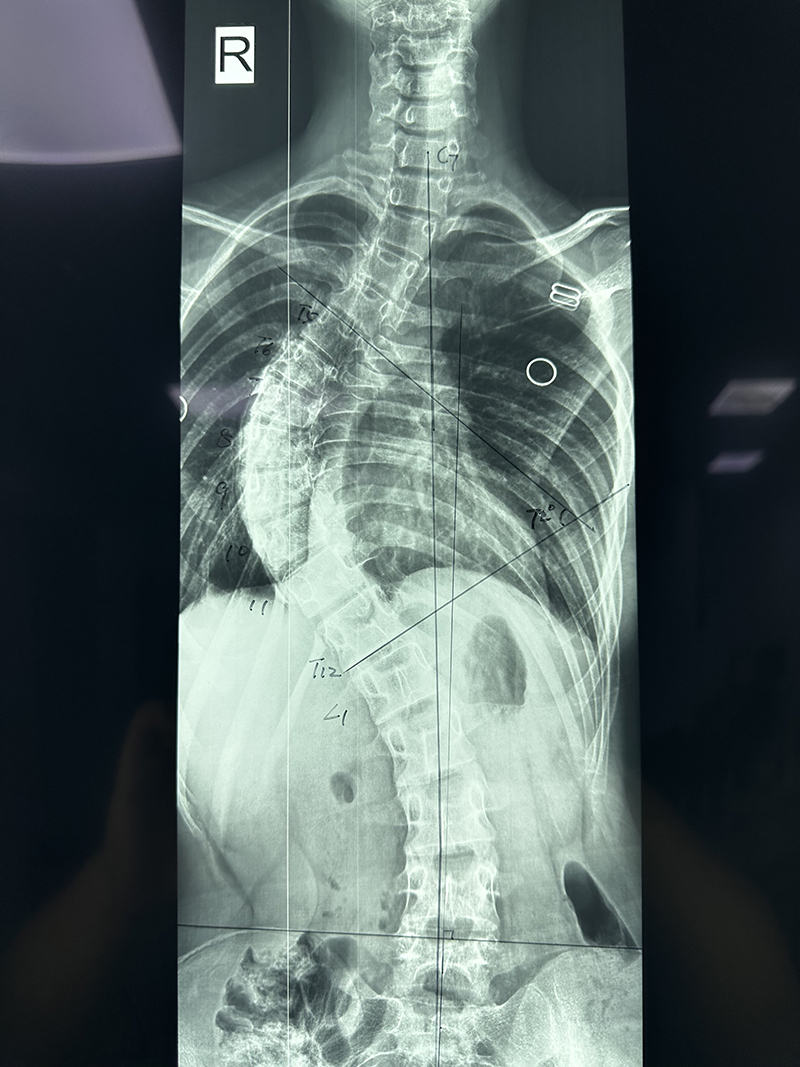

為了解決孩子的“心病”和“身病”,蕾蕾的父母帶著她來到柳州市人民醫(yī)院脊柱外科求助。住院完善相關(guān)檢查后,醫(yī)生發(fā)現(xiàn)蕾蕾脊柱側(cè)凸畸形嚴(yán)重,雙肩明顯不等高,右側(cè)肩胛骨明顯突出,右側(cè)胸前凹陷,衡量側(cè)凸的Cobb角約72°。

“患者的情況屬于青少年特發(fā)性脊柱側(cè)彎,檢查顯示脊柱呈‘S’形側(cè)彎,因為彎曲度數(shù)已超過45度,及時進行手術(shù)治療才能最大限度地糾正脊柱側(cè)彎畸形狀態(tài),在改善患者外觀的同時,避免胸腹腔臟器受到擠壓,改善患者的心肺功能!”柳州市人民醫(yī)院脊柱外科主任胡朝暉說。